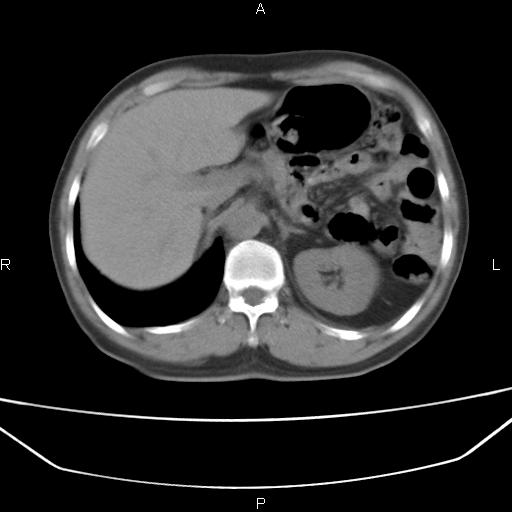

患者,男。50岁。近几日有咳嗽症状,无其他不适,既往病史无,考虑膈疝。请前辈们看看指导指导。

膈膨升,左下肺通气不良,膈肌好像还完整。

考虑左侧膈疝。

左侧膈疝。

符合隔膨升,膈肌较完整。